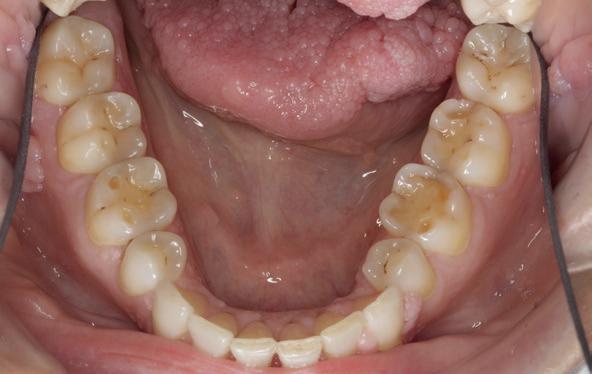

De patiënt kwam bij mij in de praktijk met een afgebroken eerste premolaar 24. Op het eerste gezicht leek het een typische casus van structurele verzwakking, mogelijk door een oude restauratie of een occlusale overbelasting. Maar een nadere analyse toonde een veel fundamenteler probleem: er was geen hoektandgeleiding aanwezig.

Normaal gesproken neemt de cuspidaat de functie van disclusie over bij laterale bewegingen, waardoor premolaren en molaren worden ontzien van over-

matige zijwaartse krachten. Bij deze patiënt functioneerde de eerste premolaar echter als een canine, wat betekende dat hij continue laterale belasting kreeg waarvoor hij simpelweg niet ontworpen was. De breuk was dan ook geen toeval, maar een voorspelbare mechanische uitkomst van een verkeerde krachtenverdeling.

In een ideale situatie zou ik eerst de occlusale verhoudingen corrigeren voordat ik een implantaat plaatste. Maar zoals vaak in de praktijk, had de patient een duidelijke wens: een snelle, vaste oplossing, zonder aanvullende restauratieve behandelingen zoals het herstellen van de hoektandgeleiding.

1. Afgebroken 24. Geen hoektandgeleiding aanwezig.